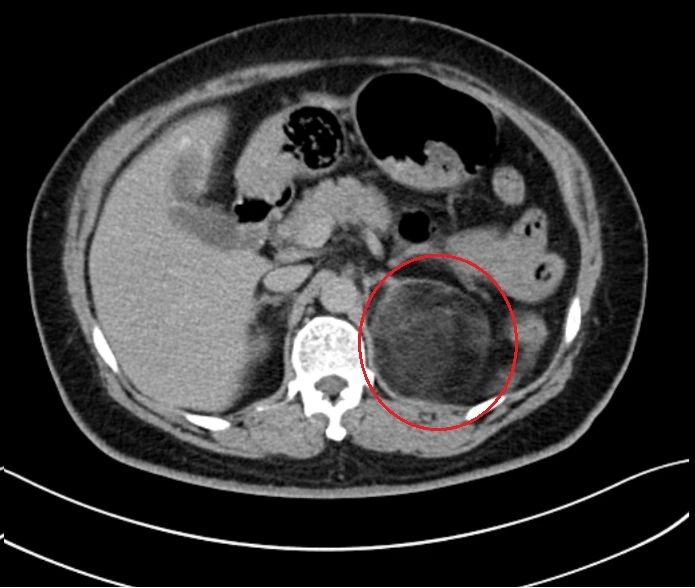

丁女士发现自己最近变胖了,而且肩背部也逐渐变得“魁梧”,但和普通的长胖不同,她的脸就像盘子一样圆,而四肢胖得并不明显,整个身体显得极不协调,最后在当地医院检查发现左侧肾上腺有一个巨大的包块,丁女士随后就诊于省内多家医院,考虑可能是肾上腺瘤,需手术切除。

几经辗转,丁女士带上各家医院的检查结果来到我院。在医生询问病史中发现,原来丁女士在四年前就已经发现了这个肾上腺占位,当时还合并有糖尿病以及高血压,而且自半年以前就反反复复的出现左侧腰痛,因为疏忽没有引起重视。随后,丁女士立即办理住院进行治疗。

从影像学上看,患者病变肾上腺已压迫同侧的肾脏,如此巨大的瘤体实属罕见,与其说肾上腺上长瘤子,不如说瘤子上长了个肾上腺,且瘤体与周围血管贴合严密,不排除有严重粘连的可能。经科室讨论后决定对该患者实施肾上腺切除。为保证患者生命安全,术前进行了为期一周的术前准备。